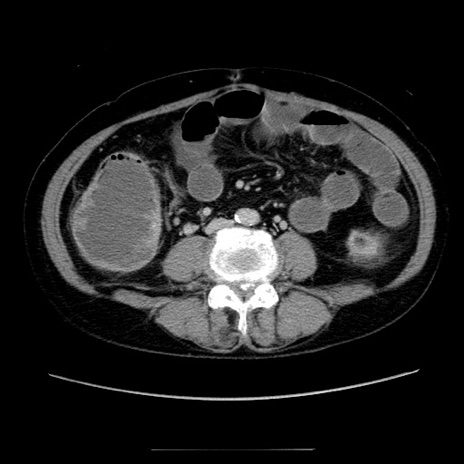

症例5(横断像)

【症例】70歳代女性

【主訴】お腹が張る

【現病歴】1週間くらい前から腹部膨満の自覚あり。昨日夜から増悪したため、本日救急外来受診。

【身体所見】意識清明、BT 36.5℃、BP 165/106mmHg、HR 80bpm、SpO2 98%、腹部:膨満、軟、自発痛・圧痛なし、触診にて不快感あり、腸蠕動音:減弱

【データ】WBC 12600、CRP 1.04